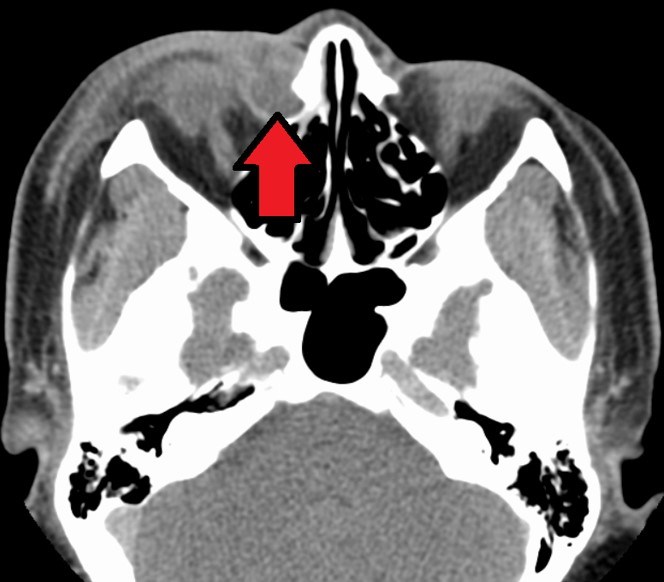

Дакриоцистит на МРТ